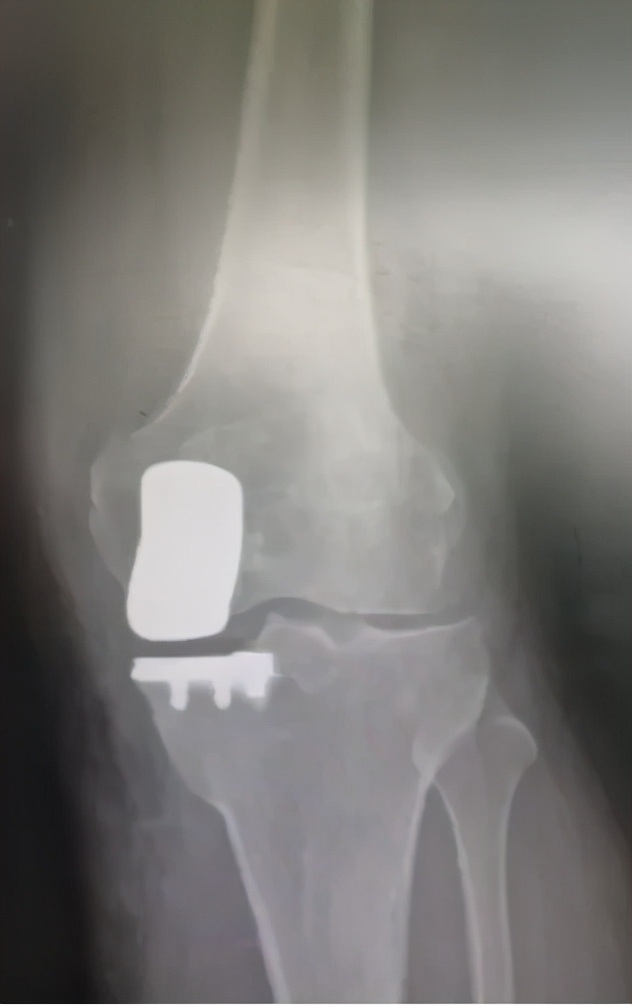

刘万军主任与团队讨论后指出,患者左膝关节内侧间室关节软骨破坏严重,外侧间室相对完好,适合膝关节单髁置换,并制定了详细的手术方案。术后患者症状消失,恢复良好。

( 术后一个月 )

(术后)